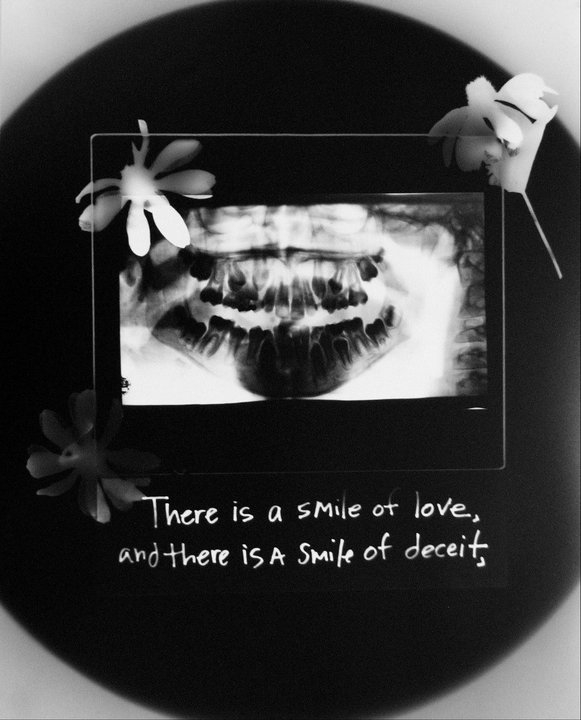

The Smile • 2019